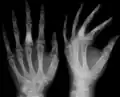

-

X-ray showing calcified enchondromas localized in finger a 37-year-old patient affected with Ollier disease -

X-ray showing enchondromas localized in the humerus of a 37-year-old patient affected with Ollier disease -

X-ray showing enchondromas localized in the lower part of the radius of a 37-year-old patient affected with Ollier disease -

Abnormal bone growth such as shortening or thickening and deformity may be observed in patients of Ollier disease. These bone lesions are visible at birth using radiography but are usually not screened or examined for until clinical manifestations present during early childhood. However, some patients may exhibit no signs of any symptoms.[1] One study found thirteen to be the mean age of diagnosis in patients with Ollier disease. In an X-ray, there would normally be the presence of several homogeneous lesions of an oval or elongated shape with bone edges that are slightly thickened.[3] With age, these lesions may calcify and appear as diffusely minute spots or stippled. Fan-like septations or streaks would be indicative of the presence of several enchondromas. Early detection and consistent and repeated monitoring is important in order to prevent and treat any potential bone neoplasms.